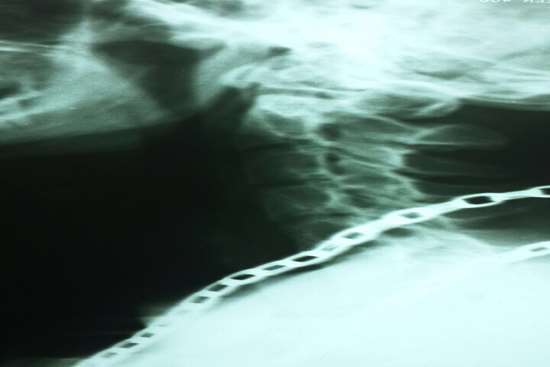

در این عمل جراحی پیچیده و 4ساعته از گردن به ستون فقرات اپروچ شد و جسم مهره C7گردنی با کمک فرز وبا استفاده از میکروسکوپ به طور کامل تراشیده شد و فشار از روی نخاع گردنی برداشته شد.(کورپکتومی)

سپس برای حفظ پایداری ستون فقرات،بجای جسم مهره C7از مش کیج EXPANDABLE از جنس تیتانیوم استفاده شد.در نهایت یک PLATE بر روی مهره آسیب دیده قرار داده شده و با کمک 4 پیچ روی مهره بالا (C6) و مهره پایین (T1) فیکس شد.